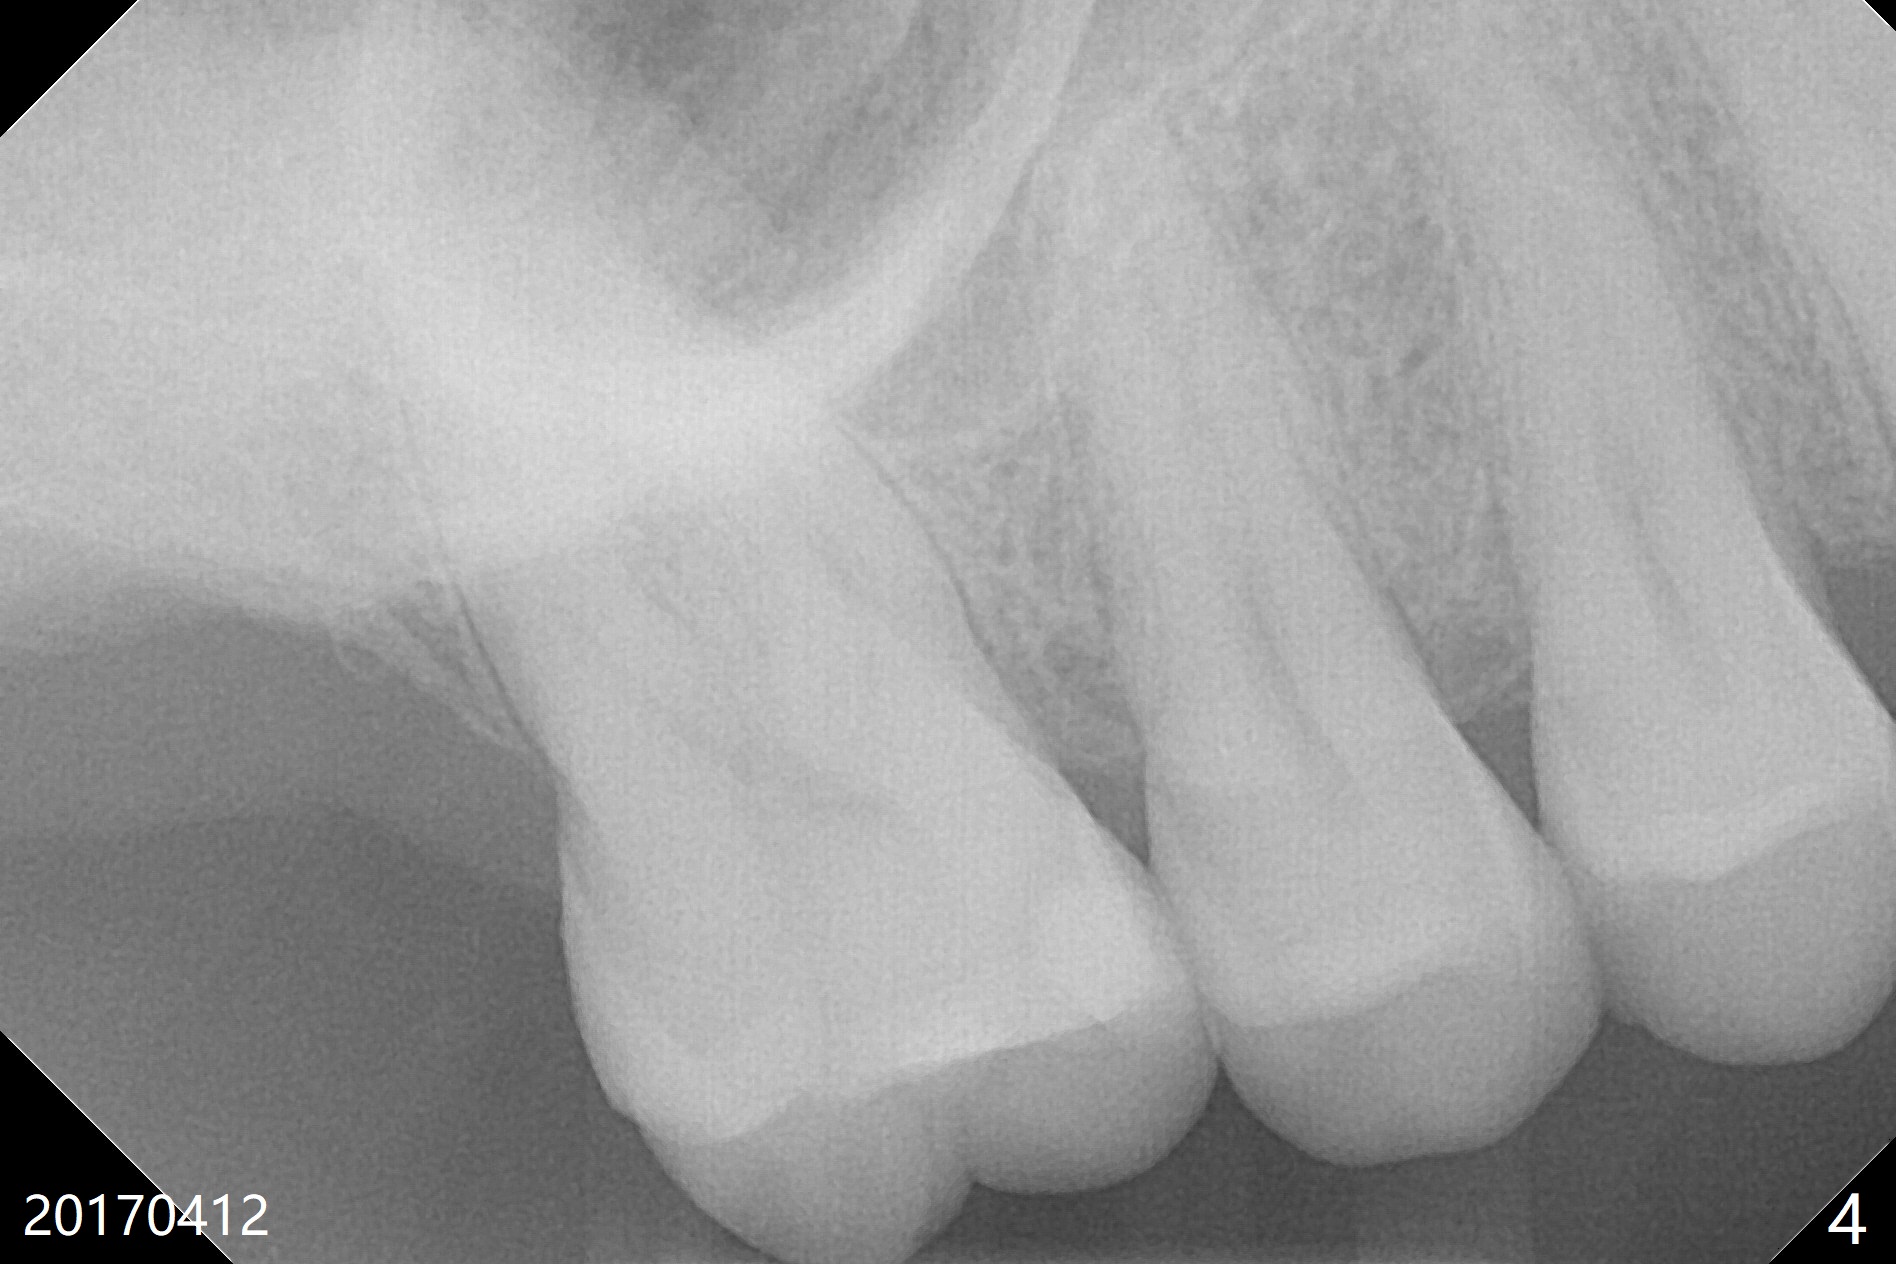

A 71-year-old man finally agrees to have an implant to be placed at #2 four years being our patient. The break point is that the crown at #30 needs recementation. The tooth #2 was missing when he presented for new patient exam (Fig.1,2). The bone loss between #30 and 31 is mild (Fig.1 *) with a small diastema (Fig.2 >). Porcelain chips at the pontic (Fig.3 >). The bone height at #2 is limited (Fig.4). The bone loss and the diastema seem to have got worse in the last 3-4 years (Fig.5). The tooth #15 has mobility with exposure of the buccal roots (Fig.6). Because of bruxism, consider flap surgery to bury the implant at #2 with guide.